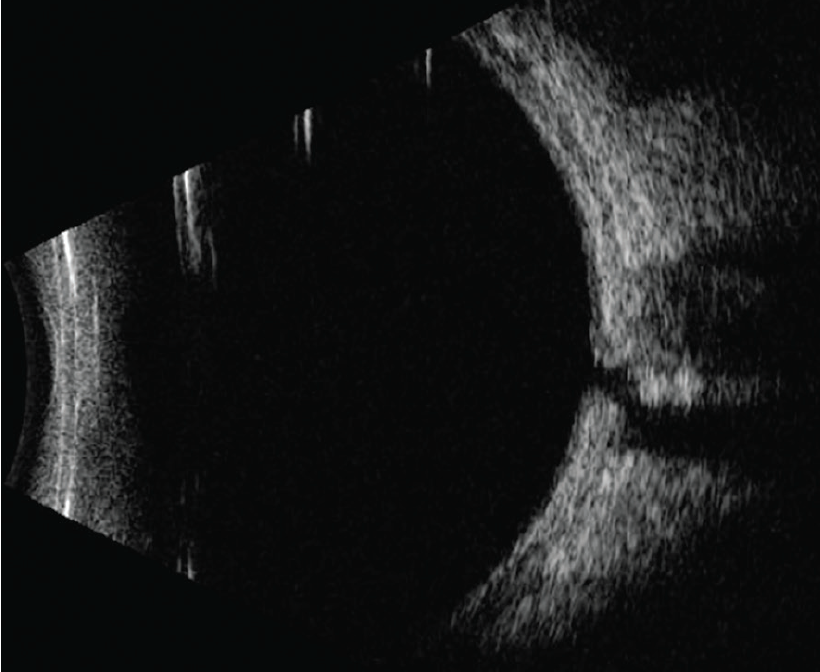

Figure 1 from Optic Disc Pit Maculopathy after Blunt Ocular Trauma Optic Disc Maculopathy Optic disk pit (odp) is a rare congenital abnormality of the optic nerve head and can lead to visual impairment when macular detachment. Optic disk pit (odp) is a rare congenital abnormality of the optic nerve head. The vast majority of cases are sporadic. A look at diagnosis and management of optic disc pits, a condition that can lead to. Optic Disc Maculopathy.

From www.semanticscholar.org